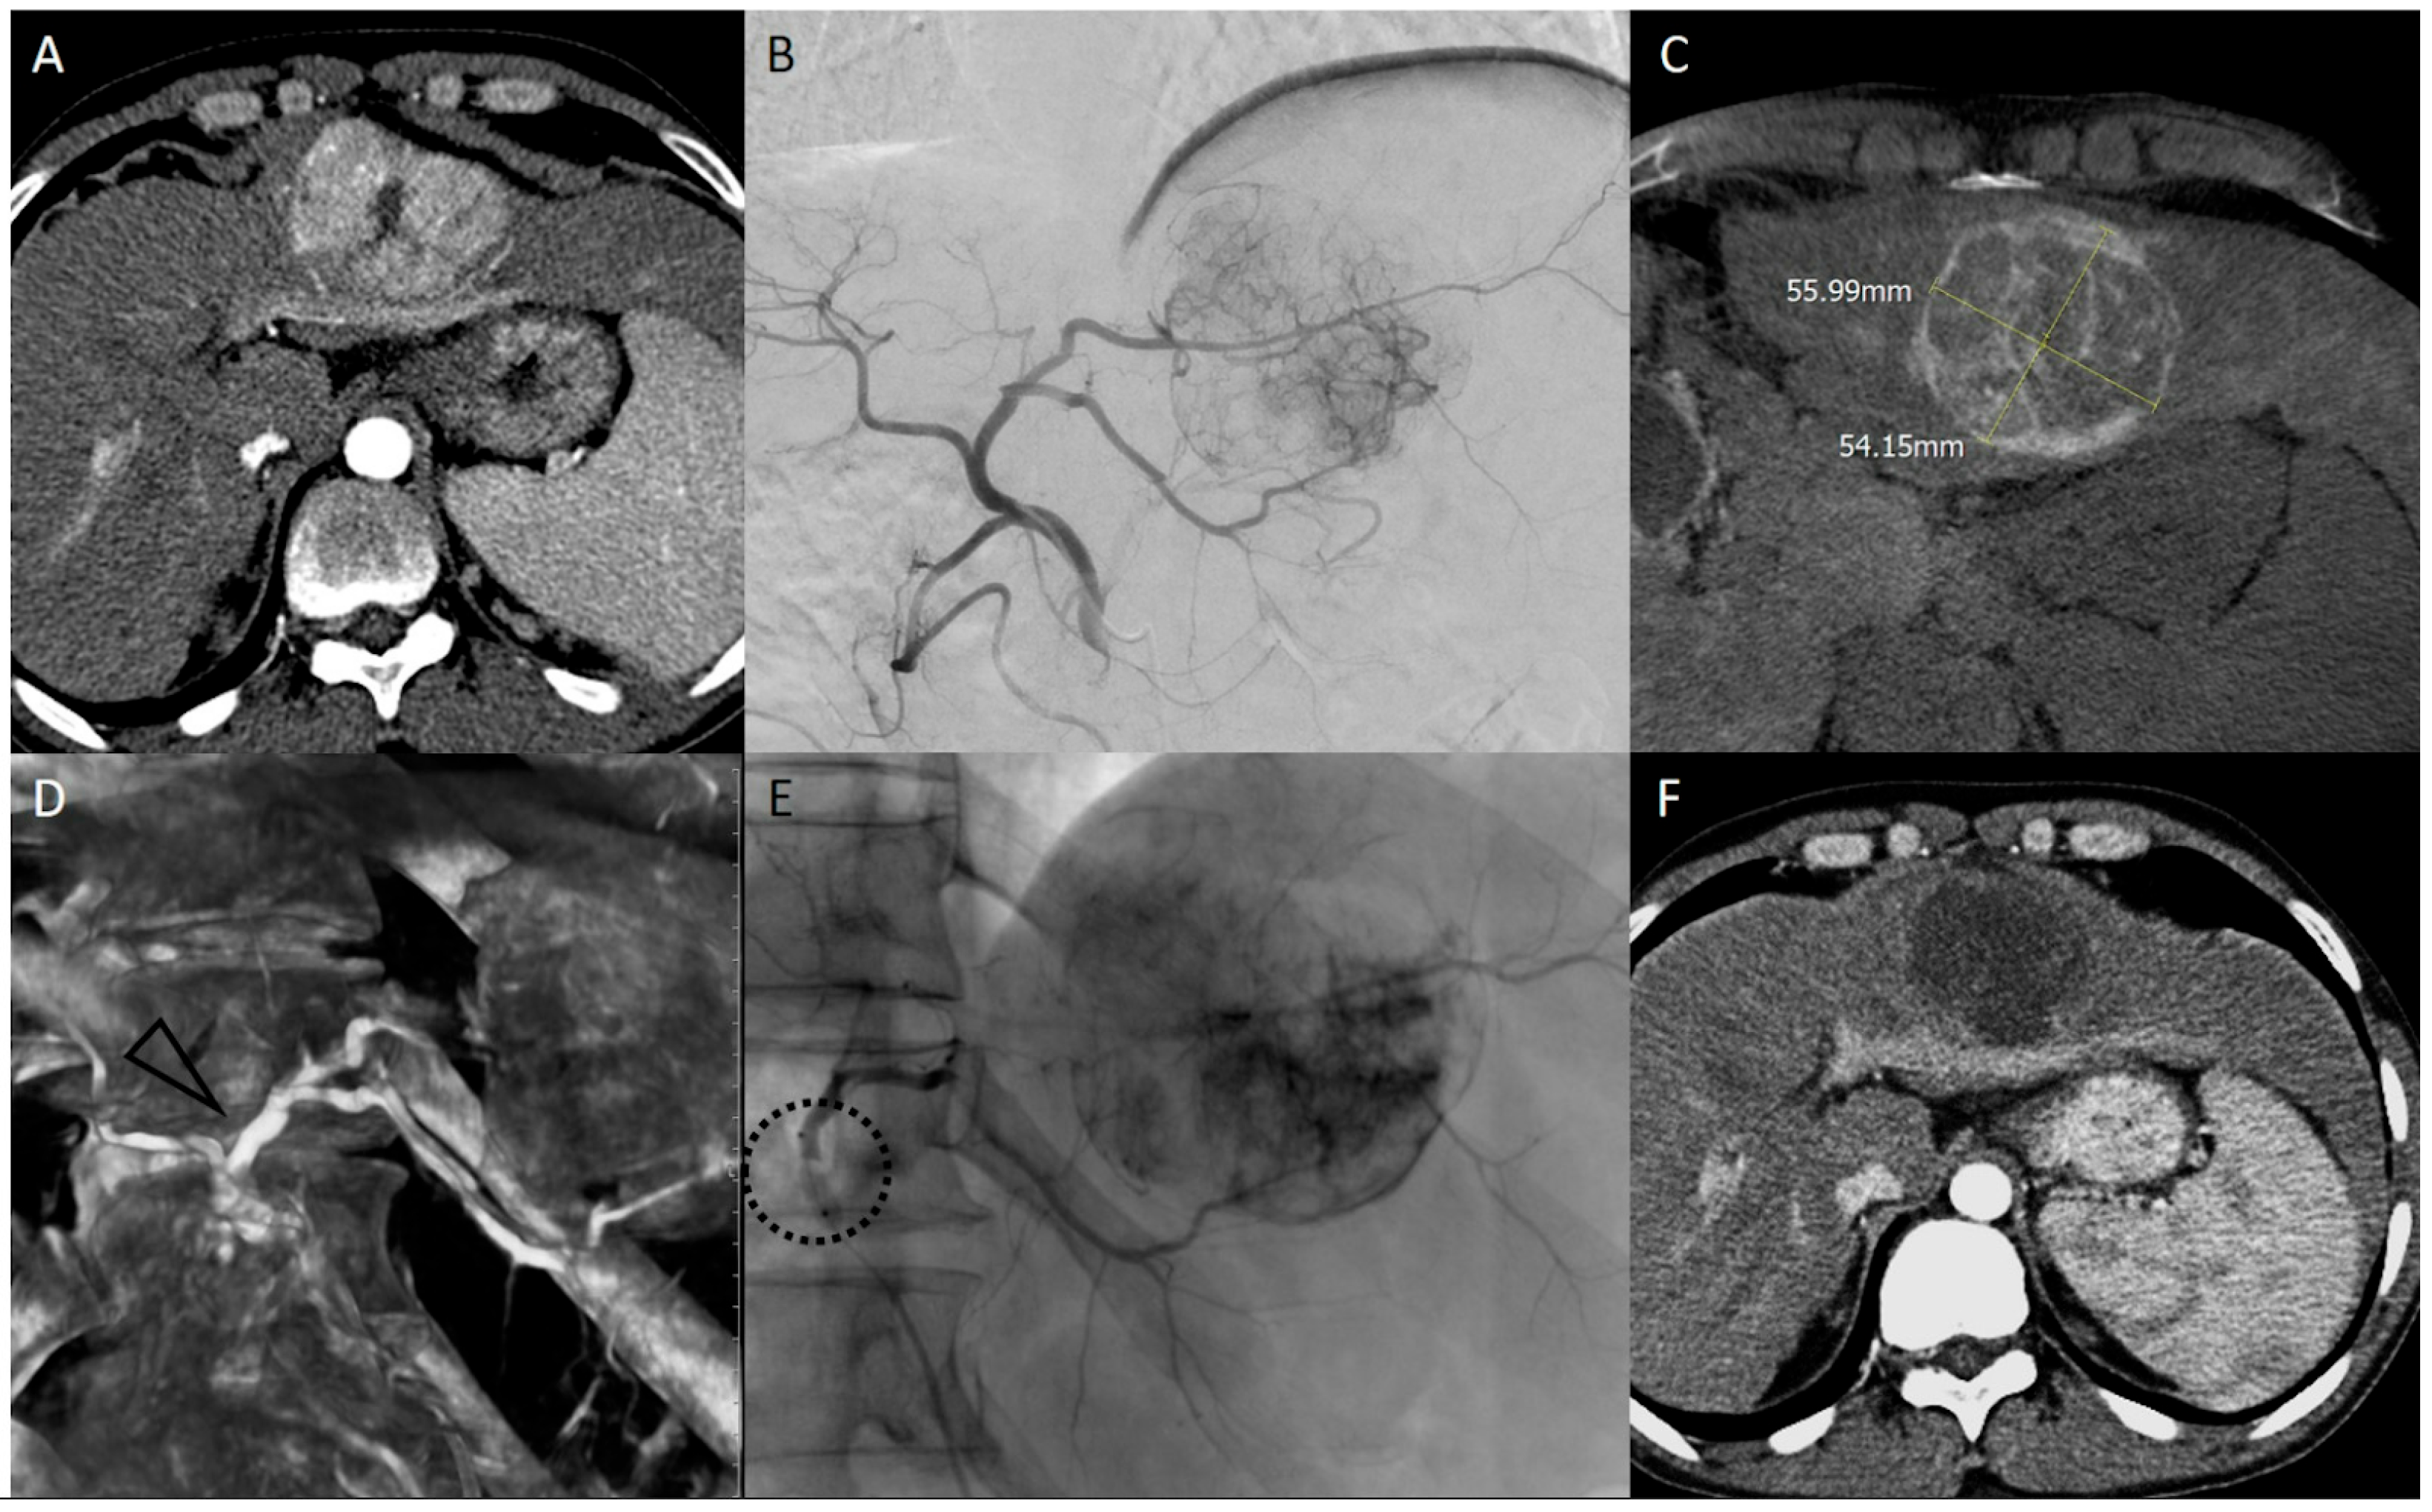

4. bTACE Technical Notes: How We Do It